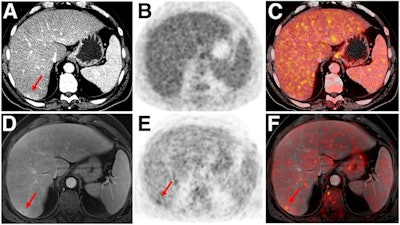

- Malignant bone disease (2.4%)

After exclusions, the researchers examined 1,003 PET/MRI scans of 918 patients. PET/MRI outperformed PET/CT in terms of providing more tumor information (26.3%), mostly in patients with malignant bone disease, followed by lung cancer, prostate cancer, and gynecologic or breast cancer. PET/MRI identified additional malignant findings in 5.3% of cases, which lead to a change in tumor, node, and metastases (TNM) staging in 2.9% of cases. PET/MRI also clearly classified indeterminate PET/CT lesions in 11% of cases.

A smaller percentage of lesions, 2.9%, were detected on PET/CT but not visible on PET/MRI. Of those lesions, 1.2% were malignant and led to a change in TNM staging in 0.5%. It should be noted PET/MRI missed a negligibly small number (0.8%) of lung metastases, which contradicts previous beliefs that the chest requires additional CT, the authors wrote. In addition, new MRI sequences such as ultrashort echo-time sequences are expected to improve lung nodule detection, which would also enhance the sensitivity of PET/MRI even further, they added.